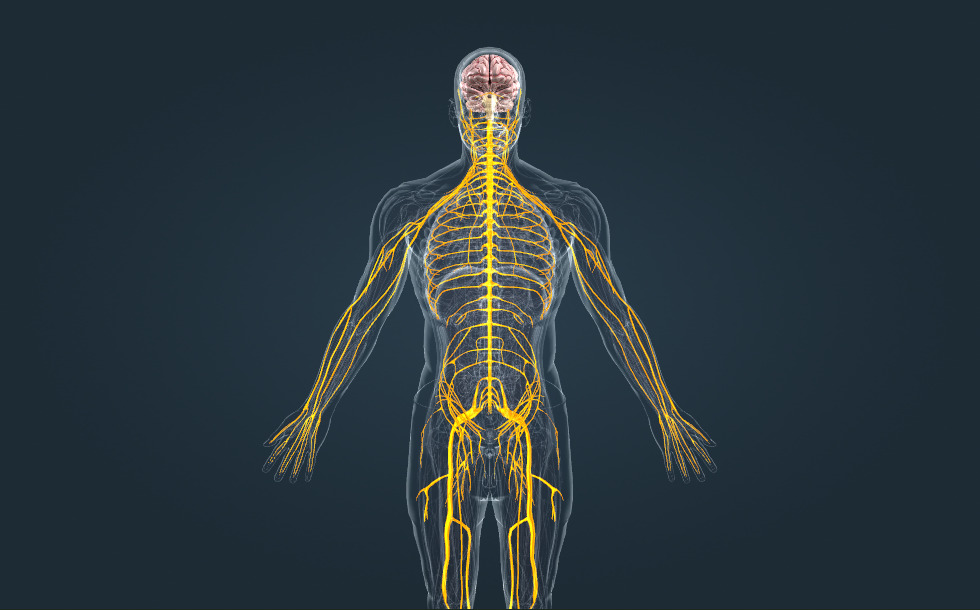

Hệ thần kinh

- não - Nó nằm trong hộp sọ.

- tủy sống - Nó nằm trong cột sống.

- dây thần kinh - Chúng gồm các sợi thần kinh giúp kết nối hệ thần kinh trung ương với các cơ quan khác.

Hệ thần kinh, cùng với hệ nội tiết, chịu trách nhiệm điều phối, điều hòa hoạt động của cơ thể. Hệ thần kinh trung ương gồm não và tủy sống, trong khi hệ thần kinh ngoại biên gồm các dây thần kinh, giúp truyền thông tin giữa hệ thần kinh trung ương và các cơ quan dưới dạng tín hiệu điện. Có 12 đôi dây thần kinh sọ não, xuất phát trực tiếp từ não và 31 đôi dây thần kinh tủy, xuất phát từ các đốt tủy.

Hệ thần kinh, cùng với hệ nội tiết, chịu trách nhiệm điều phối, điều hòa hoạt động của cơ thể. Hệ thần kinh trung ương gồm não và tủy sống, trong khi hệ thần kinh ngoại biên gồm các dây thần kinh, giúp truyền thông tin giữa hệ thần kinh trung ương và các cơ quan dưới dạng tín hiệu điện. Có 12 đôi dây thần kinh sọ não, nhô ra trực tiếp từ não và 31 đôi dây thần kinh tủy, nhô ra từ các đốt tủy.